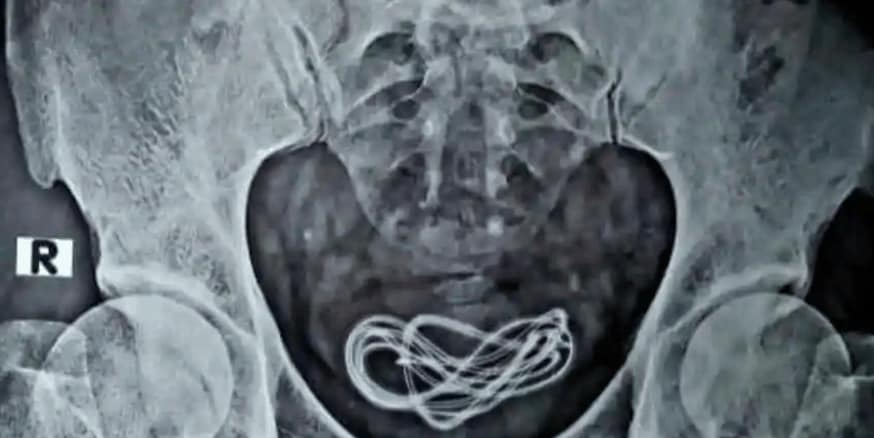

Num novo raio-x que tiveram de fazer porque não tinham encontrado nada da primeira vez, detetaram algo insólito. Falo em concreto da presença de um cabo de carregamento na bexiga e não de um auricular como tinha sido inicialmente referido pelo doente.